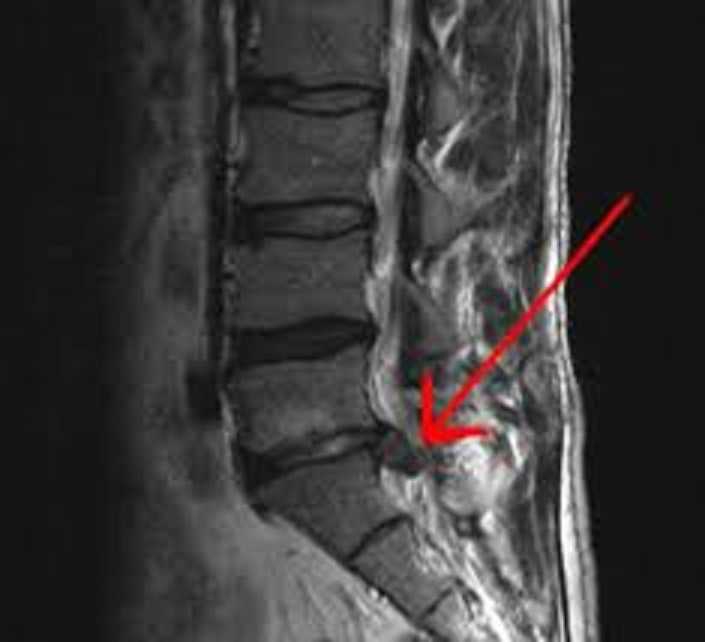

Slip disc clinic